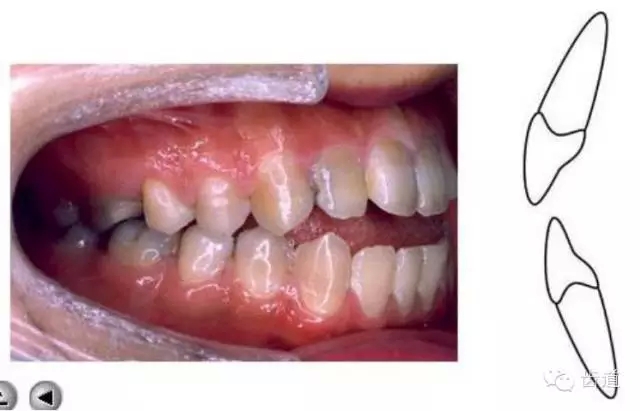

上頜第一磨牙的近中頰尖位于,下頜第一磨牙的頰溝遠(yuǎn)中

典型面形為下頜前突面形

對(duì)刃牙合 切牙合

反牙合

開(kāi)牙合

鎖牙合